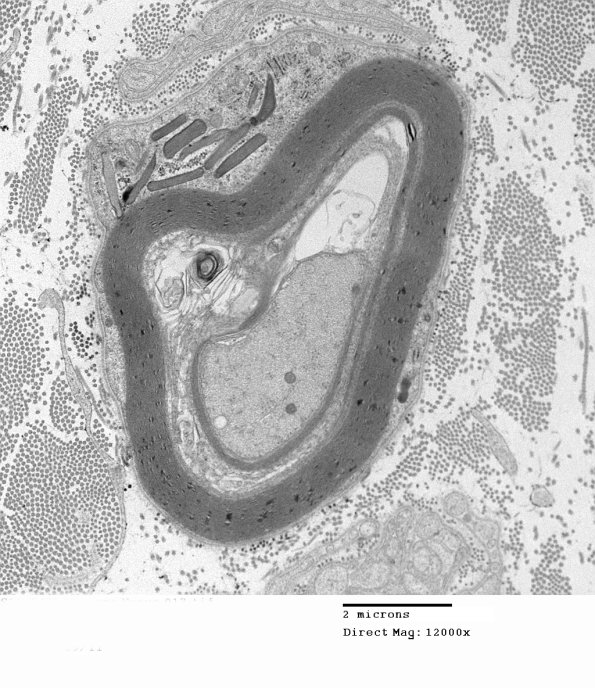

Typical disc shaped Pi granules seen largely on cross section. (electron micrograph)